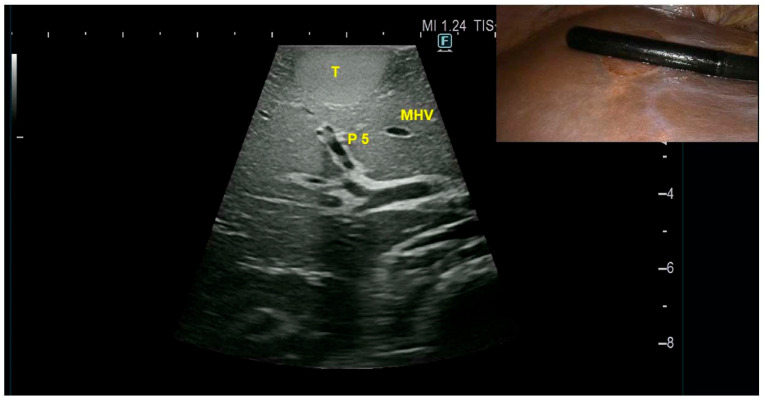

背景:肝性脾脾症(HS)是一种罕见的由脾组织异位植入引起的非生理性疾病,最常见于外伤性或外科脾切除术后。其放射学特征可能与肝细胞癌(HCC)相似,可能导致误诊和不必要的侵入性手术,如活检或肝切除术。方法:使用PubMed数据库进行文献回顾,确定所有报告的HS病例。病例介绍:我们报告一名52岁男性病例,偶然发现肝脏V段病变,最初怀疑为HCC,并有创伤后脾切除术史。患者无肝脏疾病病史。由于病变位于浅表位置,因此没有进行活检,因为存在肿瘤破裂导致出血或腹膜播种的风险。因此,患者接受了前路腹腔镜解剖切除v节段。最终病理诊断为肝内脾肿大。结论:有脾切除术史但无肝脏基础疾病的患者,特别是当影像学显示提示HCC的特征时,如动脉期高强化和门静脉冲洗时,应考虑HS作为肝脏病变的鉴别诊断。对这种实体的认识可以防止不必要的侵入性干预,并指导适当的患者管理。

Background: Hepatic splenosis (HS) is a rare para-physiological condition resulting from the ectopic implantation of splenic tissue, most commonly following traumatic or surgical splenectomy. Its radiological features can mimic those of hepatocellular carcinoma (HCC), potentially leading to misdiagnosis and unnecessary invasive procedures, such as biopsies or liver resection. Methods: A literature review was conducted using the PubMed database to identify all reported cases of HS. Case Presentation: We report the case of a 52-year-old male with an incidental finding of a liver lesion in segment V, initially suspected to be HCC, and a history of post-traumatic splenectomy. The patient had no history of underlying liver disease. Due to the lesion's superficial location, a biopsy was not performed because of the risk of tumor rupture with subsequent bleeding or peritoneal seeding. Consequently, the patient underwent upfront laparoscopic anatomic segmentectomy of segment V. Final pathology revealed a diagnosis of intrahepatic splenosis. Conclusions: HS should be considered in the differential diagnosis of liver lesions in patients with a history of splenectomy but no underlying liver disease, particularly when imaging shows features suggestive of HCC, such as arterial phase hyperenhancement and portal venous washout. Awareness of this entity may prevent unnecessary invasive interventions and guide appropriate patient management.